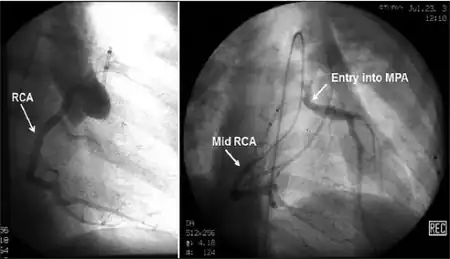

| Possible communication between left coronary artery and pulmonary artery in a 45-year-old woman with Bland-White-Garland syndrome. | |

Historically ALCAPA was diagnosed with conventional angiography. Today echocardiography is easily used. It can provide direct visualisation of the anomalous coronary artery and other associated structural abnormalities, and it can also assess myocardial function .The use of pulse and color-flow doppler can sometimes visualise reversal flow in the pulmonic artery. Other non-invasive methods used are computed tomography (CT) as well as magnetic resonance imaging (MRI) which enable a direct visualisation of the arteries as well as the myocardial viability.[3]